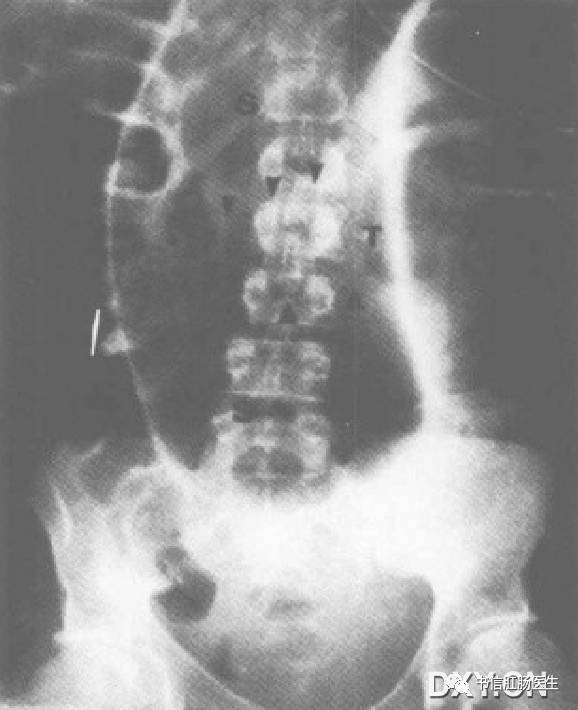

9.朝北征

★ 男性,43 岁,乙状结肠扭转。仰卧位腹部 X 线平片显示明显扩张的乙状结肠(S)上缘到腹部最上方,横结肠(T)穿过扩张的乙状结肠(S),箭头为横结肠的下缘。

■ 影像表现:仰卧位腹部 X 线平片提示明显扩张的乙状结肠上升至腹部最上缘,位于横结肠的上方。

■ 征象解析:当患者仰卧时,肠腔内的气体聚集在横结肠,是结肠最靠近腹侧的一段。横结肠穿过正中线,把腹膜腔分为结肠系膜上、下半球。因此,横结肠被认为是腹部的赤道。正常情况下,乙状结肠被限制在南半球,尾部朝向横结肠(结肠系膜下)。在乙状结肠扭转时,可见乙状结肠的顶部向头侧移位或到赤道以北(结肠系膜上),称为朝北征。

■ 讨论:肠扭转是一段肠管沿其系膜长轴旋转而造成的闭襻性肠梗阻,肠系膜过长,系膜根部附着处过窄、过松或粘连、挛缩等为肠扭转发病的解剖因素。乙状结肠和附属的肠系膜必须围绕着至少一个固定点旋转,这种旋转引起闭襻性肠梗阻及不同程度的动静脉供血不足。早期诊断迅速减压,可以阻止肠管的缺血和穿孔。

乙状结肠扭转的典型 X 线表现:卧位腹片见乙状结肠极度扩张,其肠管内径多在 10 ~15 cm,甚至可达 20 cm 以上。肠皱襞因极度扩张而不能显示。扩大的乙状结肠弯曲呈马蹄形,马蹄的圆顶高达上腹或隔下两指向下直达盆腔,马蹄的中间为两肠内壁合并构成的直线形高密度影从中腹部直伸人盆腔,称集中线征。